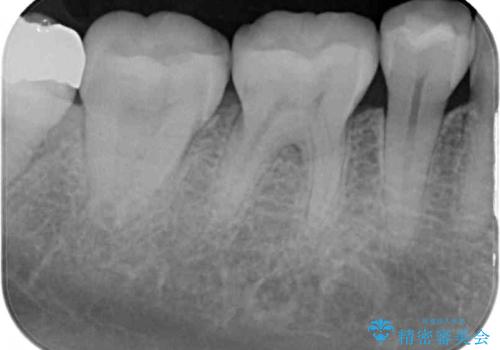

- 口を開けたときに目立ってしまう銀歯をセラミックに替えたいとのことで来院された患者様です。

上顎や親知らずにも銀歯がありましたが、今回の治療では目立つ下顎の銀歯4歯をセラミッククラウンやセラミックインレーに置き換えることにしました。